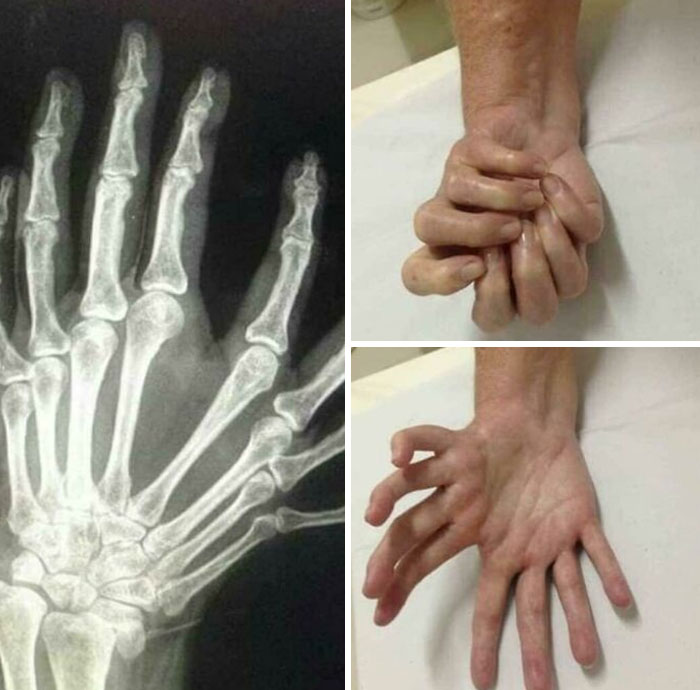

#10 Tento stav sa nazýva syndróm zrkadlovej ruky, diagnostikovaných bolo menej ako 100 prípadov a príčina je stále neznáma.